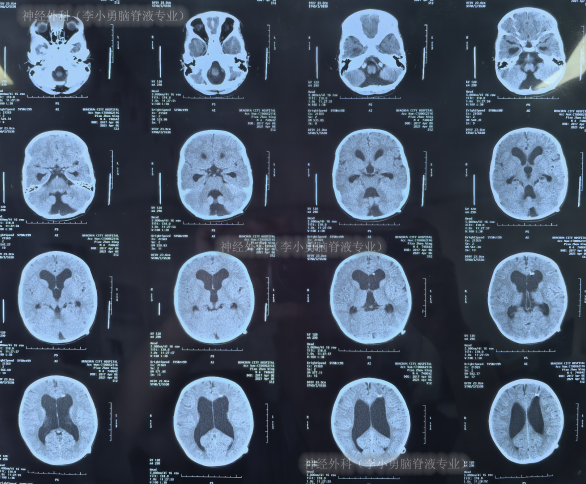

2018年7月28日(确诊脑积水3天)入院时:头颅大,头围增大至49cm,前囟门未闭合,前后径增大,张力高,眼球内聚(图-2),双侧瞳孔对光反射迟钝,间断性呕吐,呈喷射状。当天头颅CT示脑积水,合并脑室旁水肿(图-3)。

图-3:2018年7月28日头颅CT